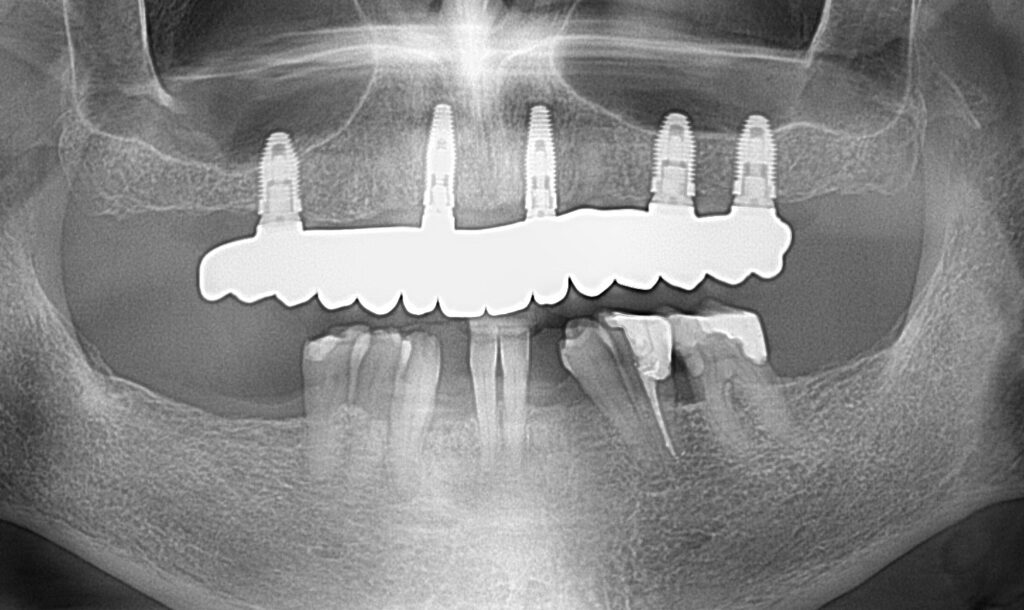

A selection of full arch fixed implant bridge patients after 5 years of wear

Oral Surgeons – Dr Han Choi, Dr Sam Goldsmith, Dr Rajiv Rajpal NSOMS

Prosthodontist – Dr Alan Payne NSOMS/Northland Prosthodontics

Dental technicians – Hosaka Takashi, DT Denture Design, Auckland, CJ Park, Project Dentistry, Auckland and Osteon Medical, Melbourne, Australia.